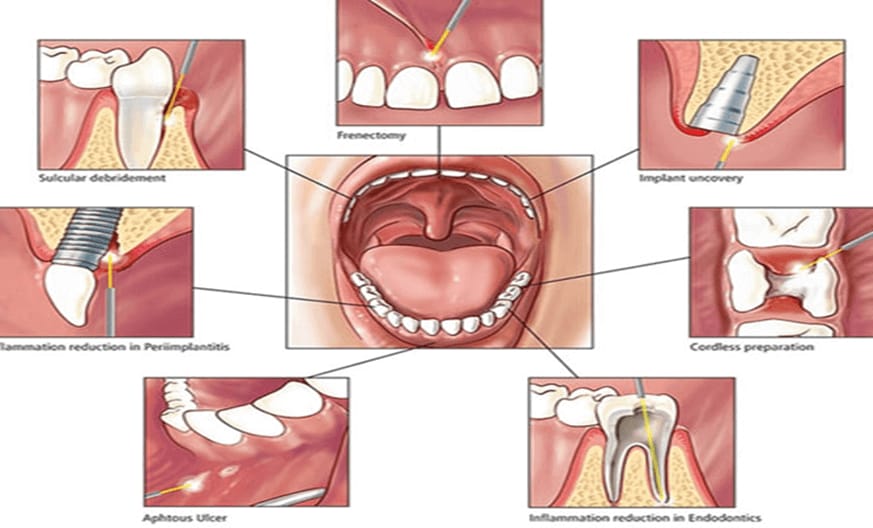

Lasers

Lasers in advanced gum treatment represent a cutting-edge approach to addressing various periodontal (gum) issues. Laser technology in dentistry is gaining popularity due to its precision, efficiency, and minimally invasive nature.

Laser gum treatment offers a modern, patient-friendly solution for managing gum disease, enhancing gum aesthetics, and improving overall dental health. It is becoming increasingly common in advanced dental practices for its numerous benefits.

Here are some key benefits and uses of lasers in gum treatment:

Minimally Invasive: Unlike traditional methods that may involve scalpels and sutures, laser gum treatments are less invasive. This means patients experience less discomfort, reduced bleeding, and quicker recovery times.

Effective in Treating Gum Disease: Lasers are highly effective in targeting and removing infected tissue around the gums caused by periodontitis (advanced gum disease). They also sterilize the area, reducing the chance of infection, and promote healthy tissue regeneration.

Gum Reshaping and Contouring: Lasers are used to reshape gum lines, especially in cases of “gummy smiles” or uneven gum lines. The laser precisely removes excess gum tissue without the need for traditional surgery.

Bacterial Reduction: One of the major advantages of laser gum treatment is its ability to kill bacteria deep in the gum pockets, helping to control infection and improve oral health.

Bone Regeneration: In more advanced cases of gum disease, lasers can be used to stimulate bone and tissue growth around teeth that have experienced bone loss due to infection.

Reduced Healing Time: Since laser treatments are less invasive and cause minimal damage to surrounding tissue, patients often experience faster healing times and require fewer follow-up visits.